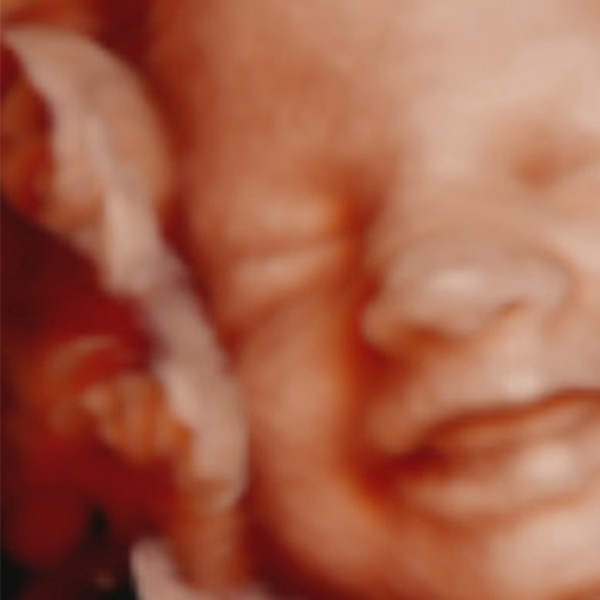

Ecografía 5D para 1 persona con fotos y vídeos de la exploración, canastilla y cheque regalo por 89,95 € en Ecox 4D-5D

Válido a partir de la semana 16 a la 39, la ecografía se verá en una pantalla de 42”

• Ecografía 5D para 1 persona con fotos y vídeos de la exploración, canastilla y cheque regalo por 89,95 € en vez de 120 €

La ecografía 5D incluye:

Centro de ecografías ubicado en el Centro de Servicios y Consultas Médicas Palmaplanas, en la Ciudad de la Salud y la Ciencia, dentro del complejo asistencial C’an Granada. Realizan ecografías 3D o 4D-5D en alta definición.